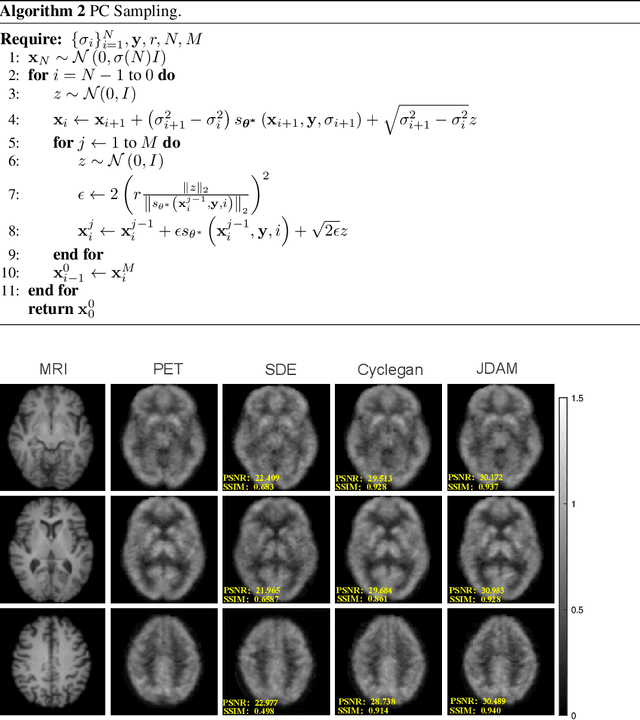

Abstract:MRI and PET are crucial diagnostic tools for brain diseases, as they provide complementary information on brain structure and function. However, PET scanning is costly and involves radioactive exposure, resulting in a lack of PET. Moreover, simultaneous PET and MRI at ultra-high-field are currently hardly infeasible. Ultra-high-field imaging has unquestionably proven valuable in both clinical and academic settings, especially in the field of cognitive neuroimaging. These motivate us to propose a method for synthetic PET from high-filed MRI and ultra-high-field MRI. From a statistical perspective, the joint probability distribution (JPD) is the most direct and fundamental means of portraying the correlation between PET and MRI. This paper proposes a novel joint diffusion attention model which has the joint probability distribution and attention strategy, named JDAM. JDAM has a diffusion process and a sampling process. The diffusion process involves the gradual diffusion of PET to Gaussian noise by adding Gaussian noise, while MRI remains fixed. JPD of MRI and noise-added PET was learned in the diffusion process. The sampling process is a predictor-corrector. PET images were generated from MRI by JPD of MRI and noise-added PET. The predictor is a reverse diffusion process and the corrector is Langevin dynamics. Experimental results on the public Alzheimer's Disease Neuroimaging Initiative (ADNI) dataset demonstrate that the proposed method outperforms state-of-the-art CycleGAN for high-field MRI (3T MRI). Finally, synthetic PET images from the ultra-high-field (5T MRI and 7T MRI) be attempted, providing a possibility for ultra-high-field PET-MRI imaging.